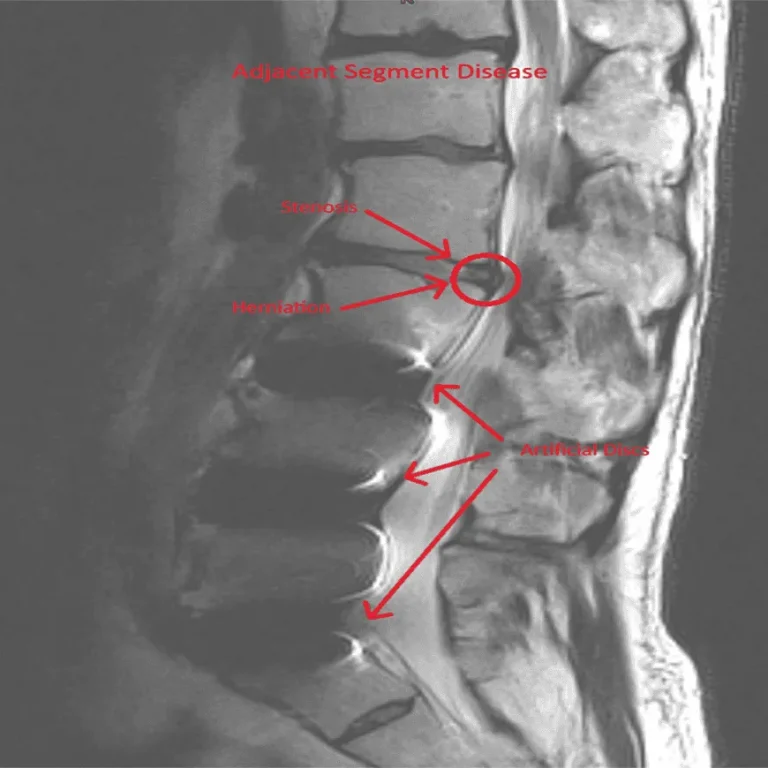

MRI of a spine showing adjacent segment disease with labels for stenosis, herniation, and artificial discs.

Adjacent Segment Disease

Spinal instability and degeneration at levels above and below the implant.